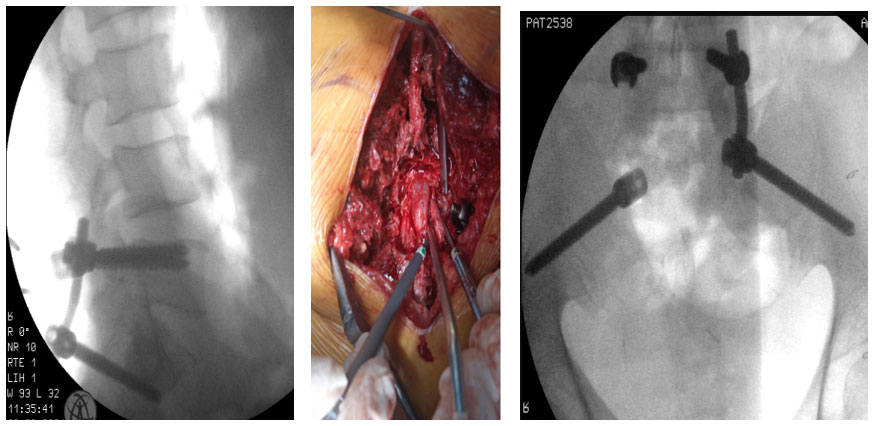

Ameliyat esnası: Skopide vidaların uygunluğu kontrol edilmekte ve omuriliğin basıdan kurtularak tamamen serbestleştirildiği görülmekte.